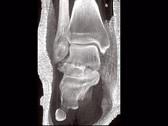

问题 男,28岁,从高处坠落后双足疼痛1月余,结合影像学检查,最可能的诊断是?(?)

选项 A.跟骨骨折 B.骰骨骨折 C.距骨骨折 D.舟状骨骨折 E.楔骨骨折

答案 C